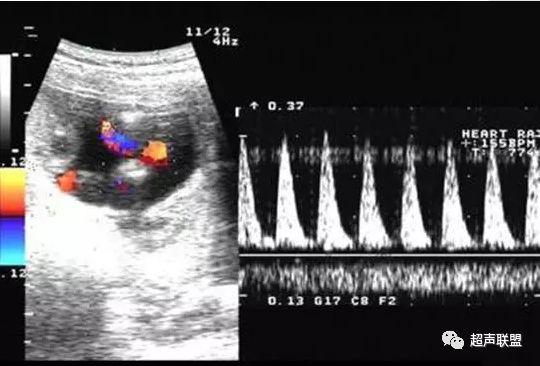

4 脐静脉频谱

胎儿宫内缺氧严重时脐静脉出现搏动。

6、脐静脉:脐静脉搏动(见于严重的胎儿宫内缺氧);

4、脐静脉搏动。

图9 脐静脉搏动